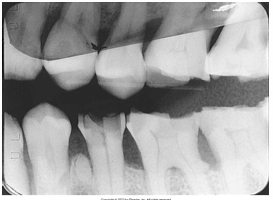

What is the problem with this Underexposed Receptor X-ray?

May occur with digital sensors or film, Image appears light or low density, Receptor was underexpose

How would you resolve this Underexposed Receptor X-ray?

Check exposure time, kilovoltage, and milliamperage settings on the x-ray machine prior to exposing the receptor